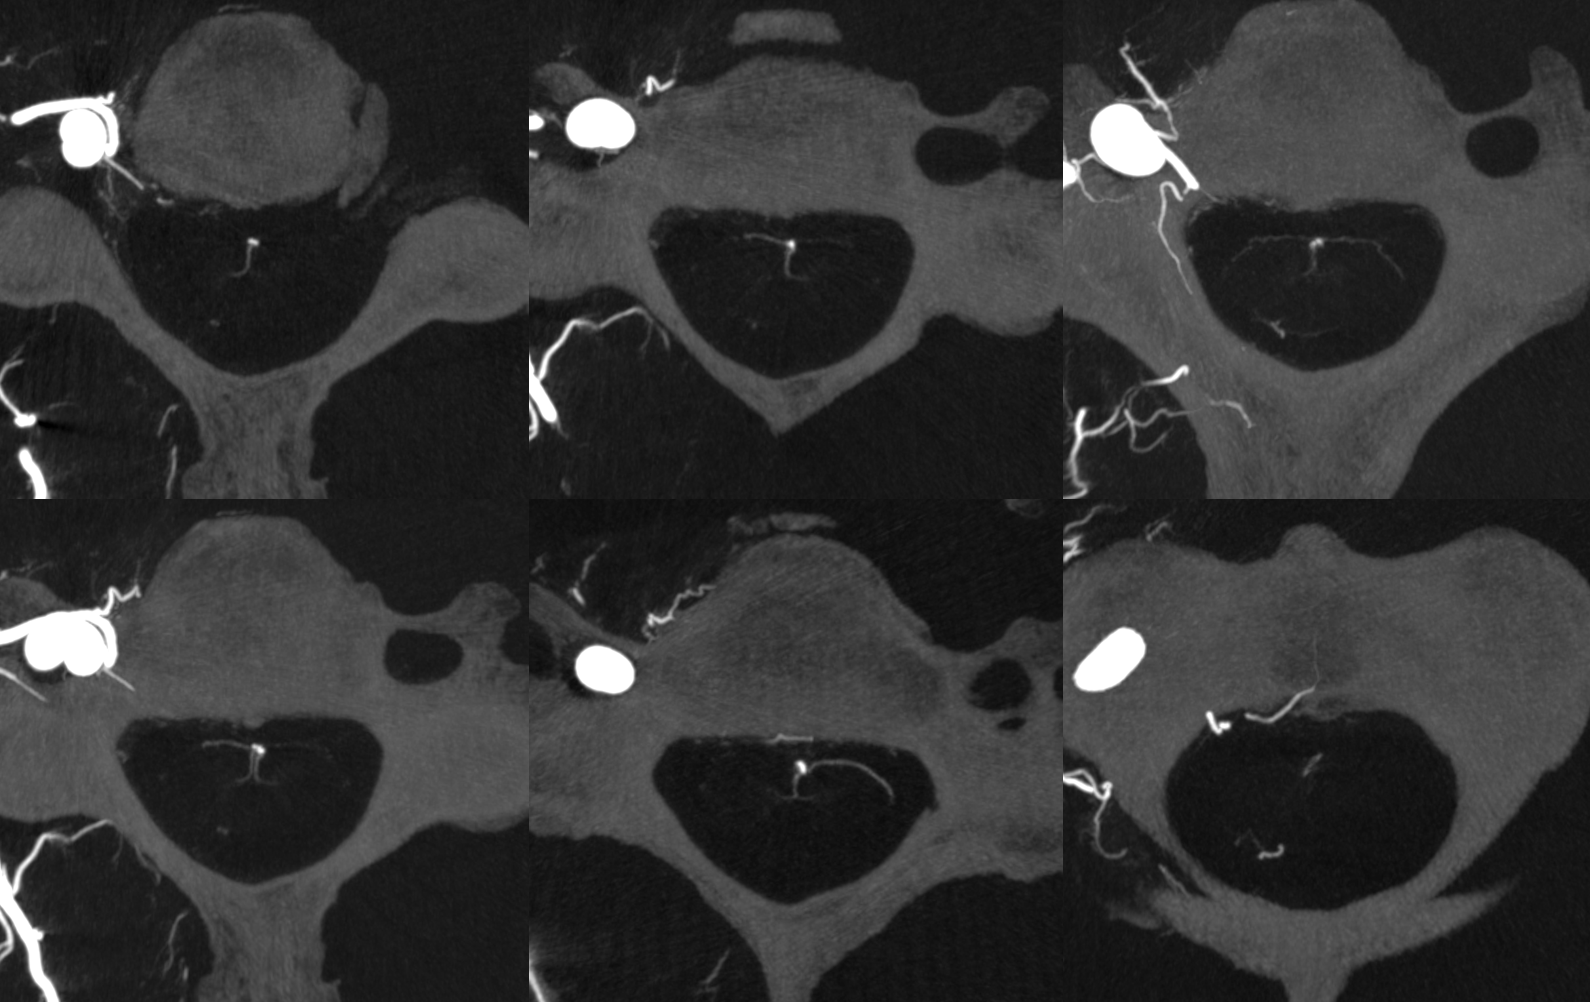

Cone Beam /Flat Panel CT evaluation of the Cervical Cord

Advances in cone beam CT are generating images with tremendous resolution throughout the spinal cord.  However, imaging thoracic and lumbar cord is particularly challenging because of the small size of the cord compared with that of the body, requiring increased x-ray doses at lower image quality.  This is much less of an issue in cervical spine, particularly when shoulders are low.  Hense, the images can be truly astounding (by 2022 standards).  Here are some examples — they are mixed arterial and venous — so many vessels are veins — see “Spinal Venous Anatomy” page.

Axials are super!  See multiple radicular veins draining cord?  Also sulco-comissural (ventral median sulcus) arteries and veins

Axial MIPs